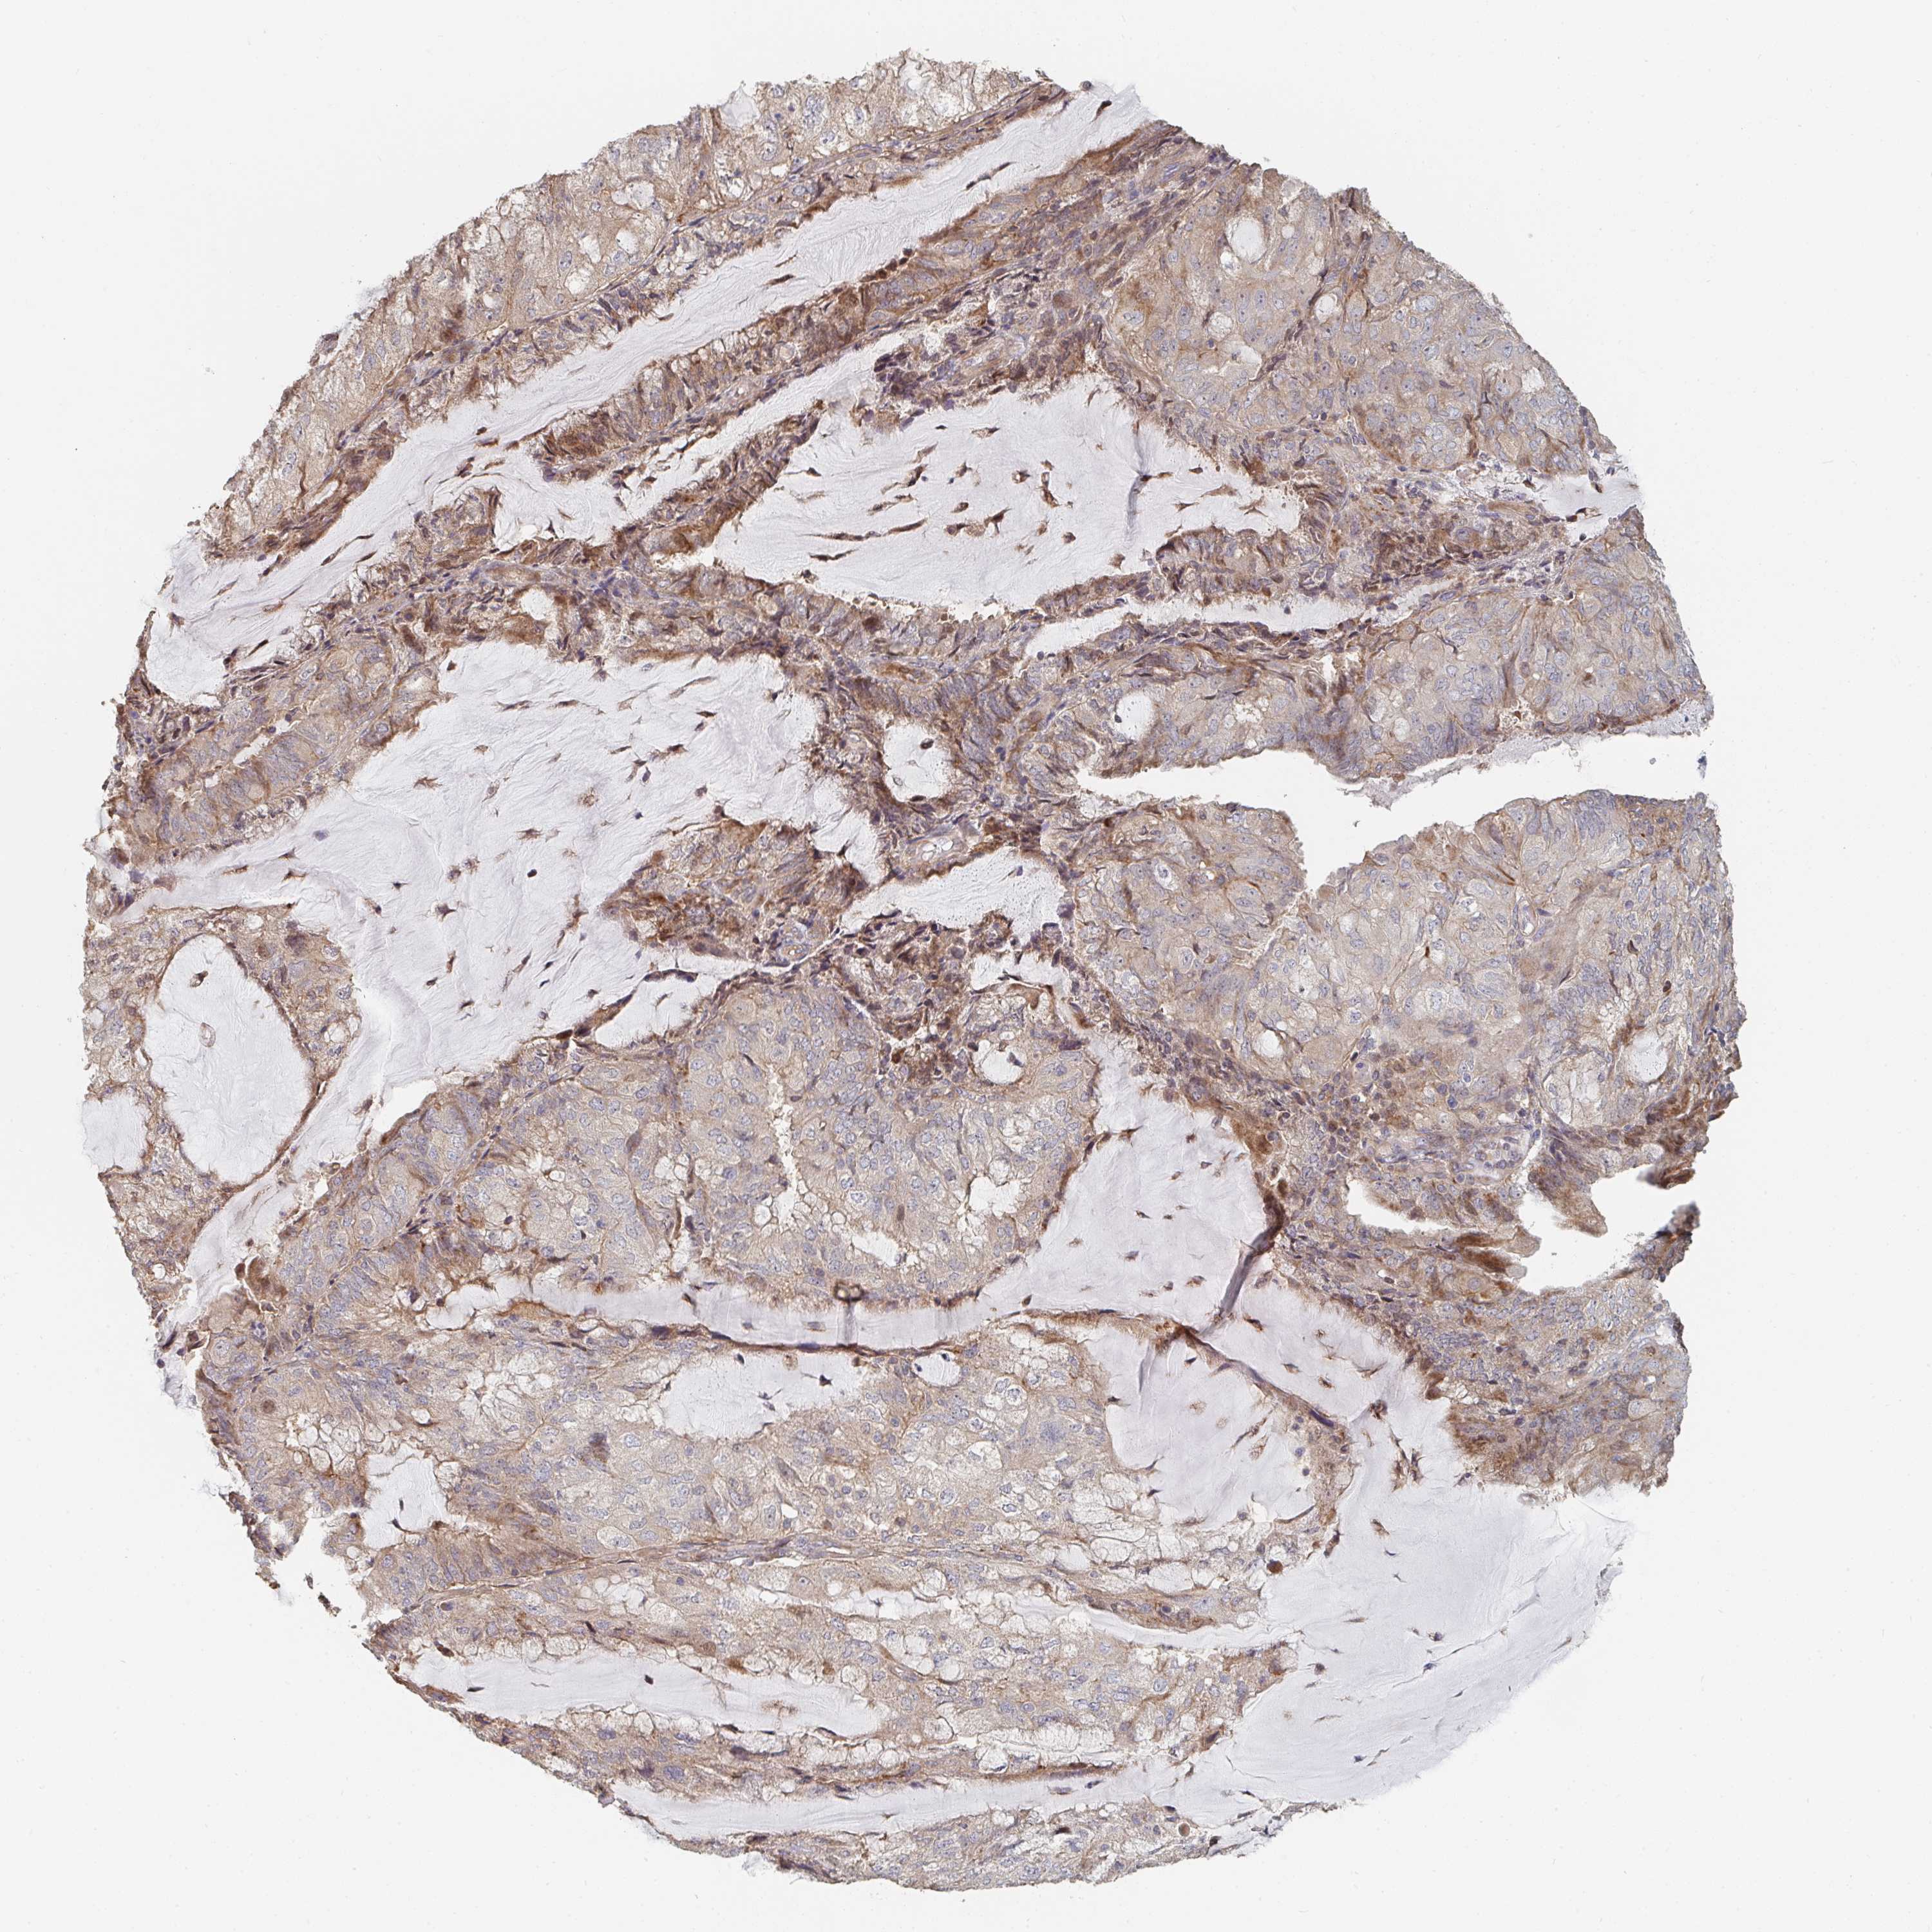

ENDOMETRIAL CANCER - Protein expressioni

A mouse-over function shows sample information and annotation data. Click on an image to view it in a full screen mode. Samples can be filtered based on level of antibody staining by selecting one or several of the following categories: high, medium, low and not detected. The assay and annotation is described here.

Note that samples used for immunohistochemistry by the Human Protein Atlas do not correspond to samples in the TCGA dataset.

Antibody stainingi

Antibody staining in the annotated cell types in the current human tissue is reported as not detected, low, medium, or high, based on conventional immunohistochemistry profiling in selected tissues. This score is based on the combination of the staining intensity and fraction of stained cells.

Each image is clickable and will lead to virtual microscopy that enables deeper exploration of all samples and also displays staining intensity scores, fraction scores and subcellular localization as well as patient and tissue information for each sample.

Antibody HPA031335

Antibody CAB004076

Antibody CAB080153

Antibody CAB080157

Staining

High

Medium

Low

Not detected

Intensity

Strong

Moderate

Weak

Negative

Quantity

>75%

75%-25%

<25%

None

Location

Nuclear

Cytoplasmic/membranous

Cytoplasmic/membranous,nuclear

Adenocarcinoma, NOS

Neoplasm, malignant, NOS

Carcinoma, NOS

Adenocarcinoma, metastatic, NOS